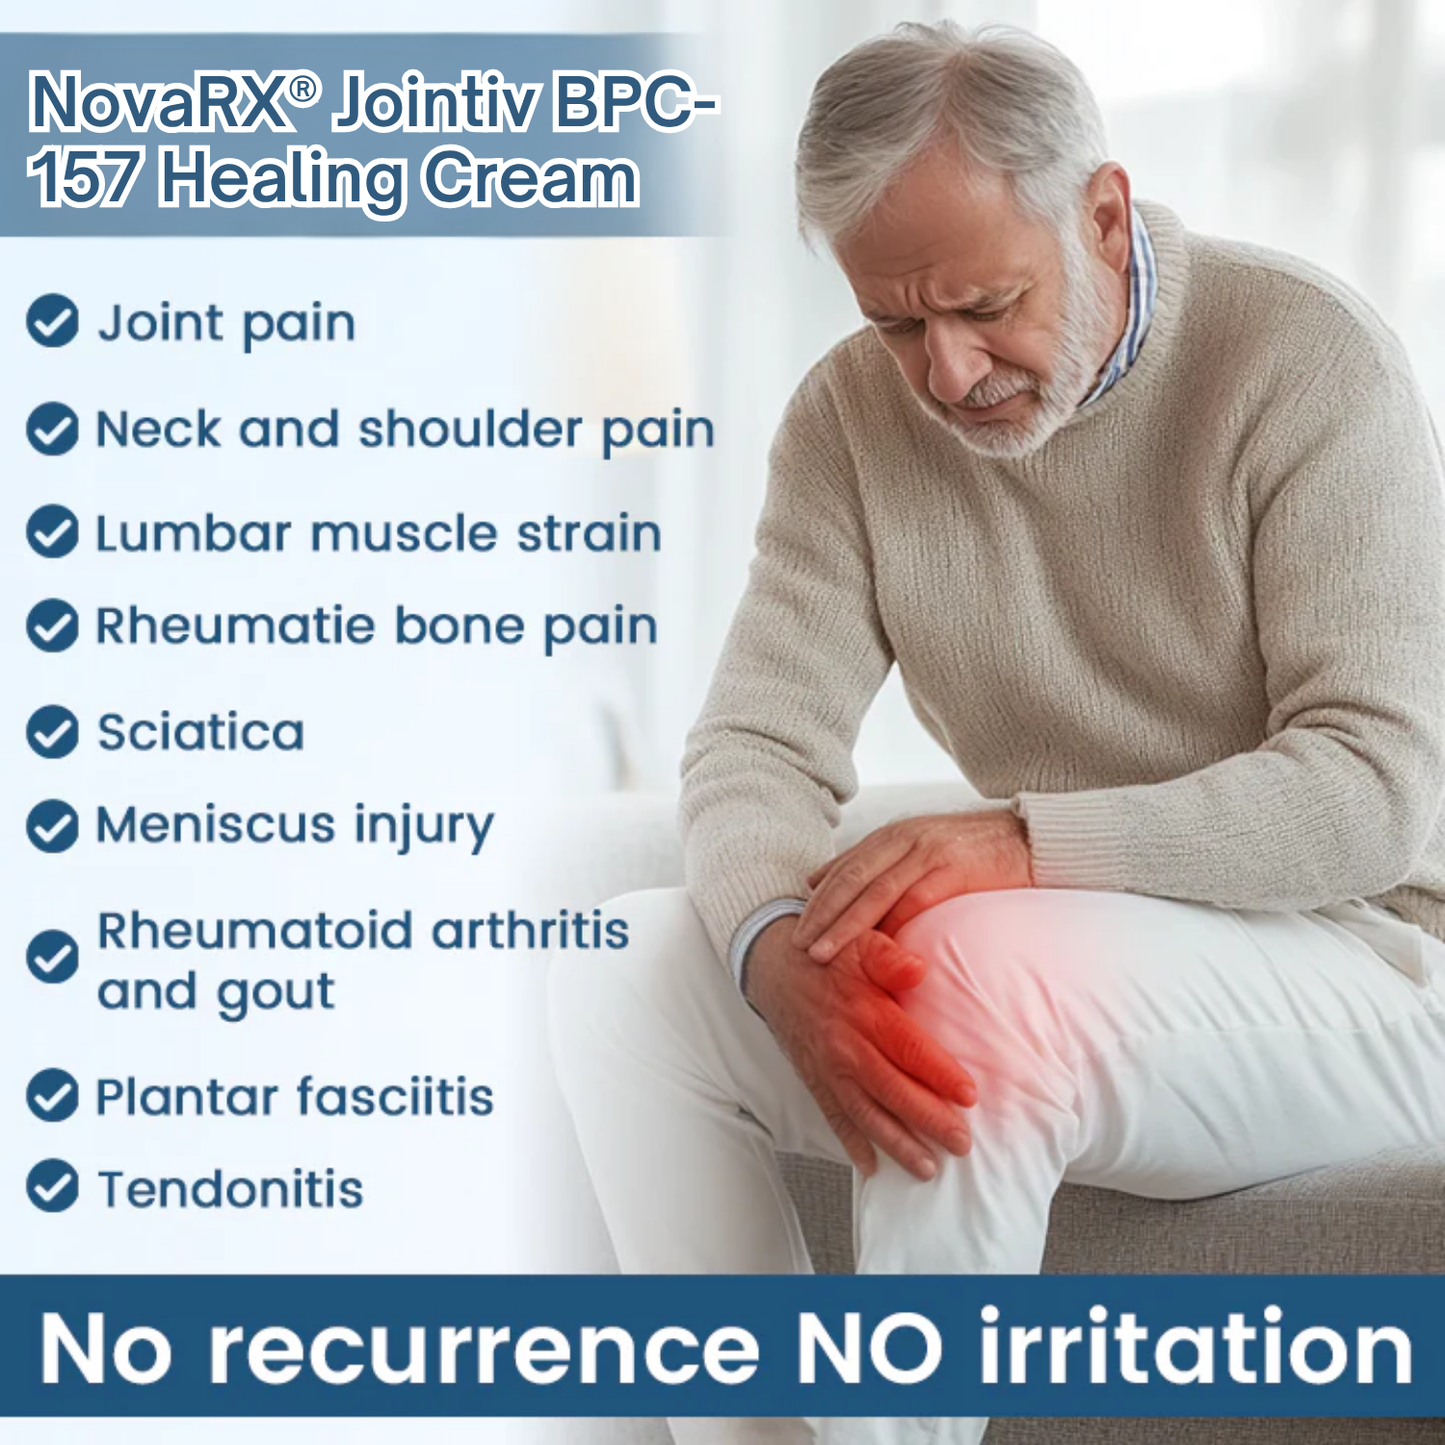

Every day, your joints absorb pressure, support movement, and keep you going — but age, injury, and inflammation slowly wear them down. Cartilage thins, tissues become inflamed, and flexibility fades. Over time, this results in stiffness, pain, and restricted mobility that steal your comfort and freedom.

The Hidden Dangers of Joint Disease